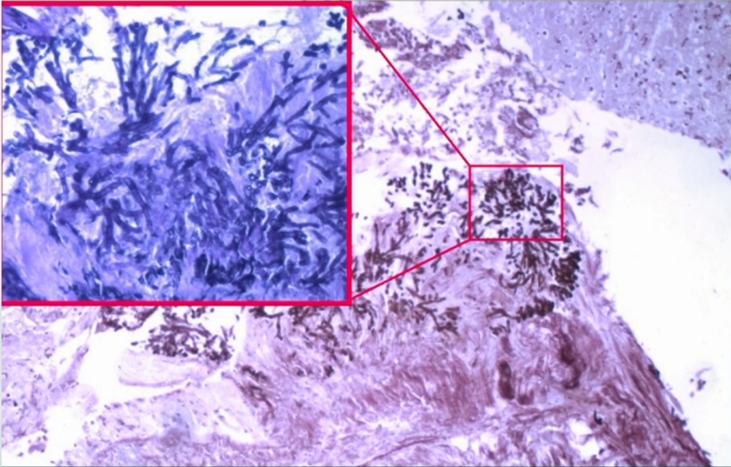

图片

第12天,病理检查结果显示气道腔内可见大量曲霉菌菌丝,侵袭至黏膜内。所以该病例是侵袭气道的曲霉菌感染,引起COPD患者严重喘息。最终的诊断是AECOPD,伴侵袭性曲霉菌气管支气管炎(IATB)。

回顾该病例的诊治过程:患者做了两次胸部CT,肺内并无明显的曲霉菌感染,通过气管镜检查发现气道内的微小病变,这是曲霉菌侵袭气道黏膜所致。患者有吸入激素和近期短期的全身系统激素使用情况,最终通过病理检查确诊IATB,给予抗真菌药物治疗后,短期内(1周左右)病情得以缓解。1年后随访,患者一般状态较好,病情未再反复,亦未再使用抗真菌药物。

入科诊断为AECOPD,Ⅱ型呼吸衰竭,肺源性心脏病,2型糖尿病,急性肾功能不全。患者入院时,急诊胸部CT可见其双肺肺气肿表现,12月20日,急诊插管上呼吸机后,在肺内仍未见明确的斑片渗出影。12月20—21日行气管镜检查,气管镜下可见左肺各叶段支气管黏膜充血水肿、分泌物填充伴伪膜形成,随后患者左肺逐渐出现斑片渗出影,并逐渐加重,患者同时出现急性肾衰竭和消化道出血,以及神志障碍和休克。气管镜下留取黏膜组织标本可见真菌菌丝侵袭气道黏膜局部,引起感染。积极给予两性霉素B和伏立康唑抗感染治疗,但患者最终因多脏器功能衰竭而死亡。

回顾该病例的救治过程:住院第2天行气管镜检查,可见大量的黏稠痰液,吸痰后可见局部黏膜充血,间嵴水肿,有伪膜和白斑。病理检查发现黏膜中大量菌丝侵袭至黏膜内。影像学检查提示COPD患者出现急性加重时,肺内并无明确病变,随着病情进展,曲霉菌感染从气道内逐渐向肺实质播散。当机体免疫功能受到抑制时,曲霉菌会进一步向肺实质播散,并引起严重的自身免疫相关损伤,最终导致多脏器功能衰竭,预后不良。早期启动抗真菌治疗的疗效尚可。当进展至IPA时,即使采用联合治疗,预后可能也不容乐观。